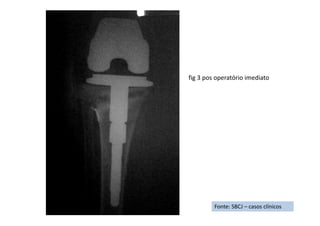

• Diagnóstico(s): Luxação do joelho direito com lesão ligamentar complexa.

• Tratamento(s): (continuação)

Realizou-se a cirurgia com uma semana, sendo o procedimento escolhido a realização de 2 incisões amplas. A

primeira ânteromedial e parapatelar medial, por onde se abordou toda a região anterior e medial do joelho e a

segunda ânterolateral, centrada no epicôndilo lateral, onde se abordou a região lateral, posterolateral e

posterior do joelho.

Foram realizados a reconstrução do ligamento cruzado posterior por via aberta, com enxertia do terço central

do tendão patelar fixada com 2 parafusos de interferência acrescidos de uma fixação em poste com parafuso e

arruela na tíbia. Feita a reinserção da avulsão do ligamento cruzado anterior com pontos transósseos e

amarrilho direto na tíbia proximal.

Na região lateral e pósterolateral foram feitos reinserção transóssea do bíceps femoral e dos ligamentos

colateral lateral e complexo arqueado na cabeça da fíbula (o tendão poplíteo estava íntegro); reinserção da

cápsula ânterolateral com âncora metálica de 5,0mm e reinserção do tracto ileotibial no tubérculo de Gerdi com

uma âncora metálica de 5,0mm.

Na região medial do joelho foram realizadas reinserção da cápsula ânteromedial e do ligamento colateral medial

profundo e dos ligamentos meniscotibiais à tíbia com 2 âncoras de 5,0mm e reinserção do ligamento colateral

medial superficial com um agrafe de blount à tíbia medial, de onde tinha se rompido. Seguimento ("Follow